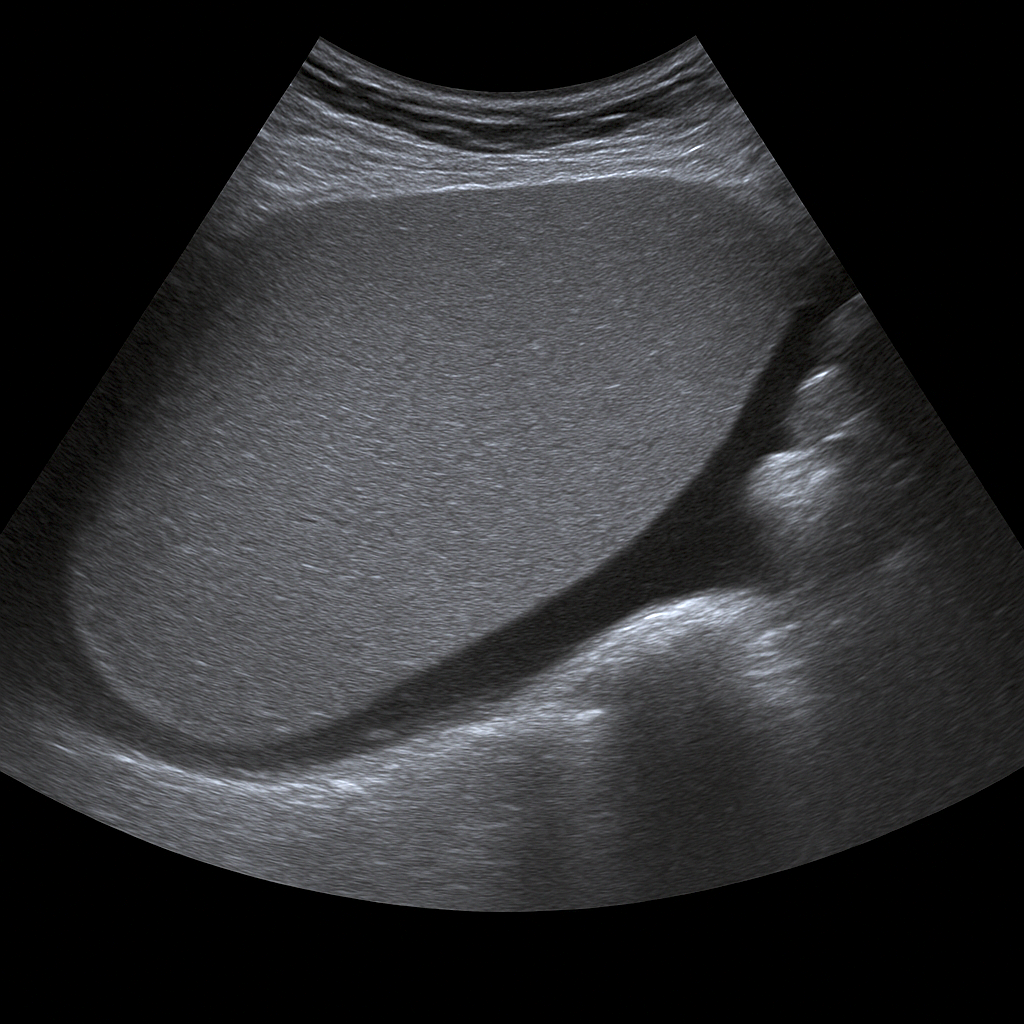

- Ultrasound of the liver shows fatty liver, cysts, tumors and structural changes in the liver.

- Recommended for elevated liver values, abdominal pain or suspected liver disease.

- Quick, painless and radiation-free examination of the liver's structure and blood flow.

- Written opinion and recommendation from a specialist doctor are included.

- Ultrasound liver with elastography measures the stiffness of the liver and assesses the degree of fibrosis or cirrhosis.

- Recommended for fatty liver, hepatitis or suspected chronic liver disease.

- Fast, painless and radiation-free method – an alternative to liver biopsy.

- Written opinion and recommendation from a specialist doctor included.